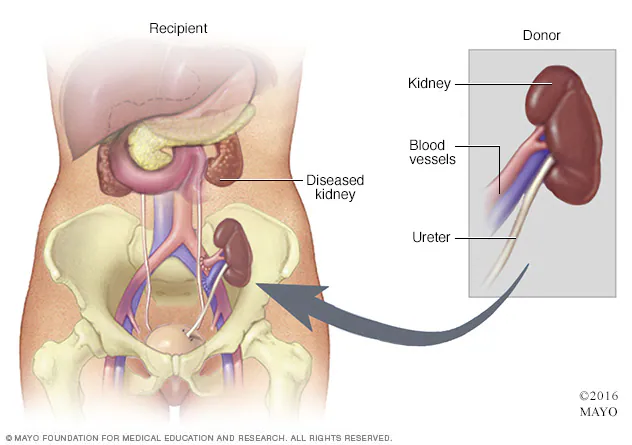

Entenda lista de espera, doador vivo, riscos pós-cirurgia e expectativas do transplante.